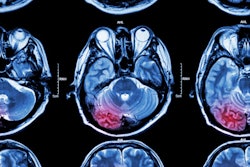

Artificial intelligence (AI) algorithms can determine from multiparametric MRI exams if a stroke patient's symptoms began within 4.5 hours -- the recommended window of time for a patient to be treated with thrombolysis, according to research published online January 28 in Stroke.

Intravenous thrombolysis is recommended up to within 4.5 hours of symptom onset in stroke patients, but approximately 25% of patients don't know when their strokes began and are therefore excluded from that treatment. Multiparametric MRI may be useful as diffusion-weighted imaging (DWI) detects reduced apparent diffusion coefficient (ADC) of ischemic lesions within minutes of stroke, while fluid-attenuated inversion recovery (FLAIR) shows a net increase in water content within one to four hours, according to the researchers.

"Thus, a mismatch of signals on DWI and FLAIR may be used as tissue clock," they wrote.

However, a DWI-FLAIR mismatch doesn't necessarily mean that the patient has actually had a stroke within 4.5 hours, according to the authors. What's more, human readings of DWI-FLAIR signals have been characterized by low-to-moderate intra- and interreader reliability.